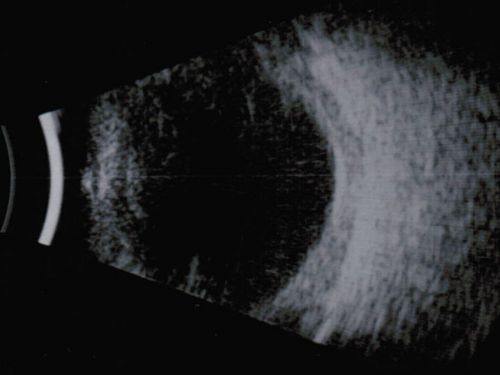

Nanopthalmous (Microphthalmous) Chorioretinal Folds and Choroidal Thickening Both Eyes B-Scan Ultrasound

Nanophthalmous Microphthalmous Thick Sclera Choroidal Congestion - Chorioretinal Folds